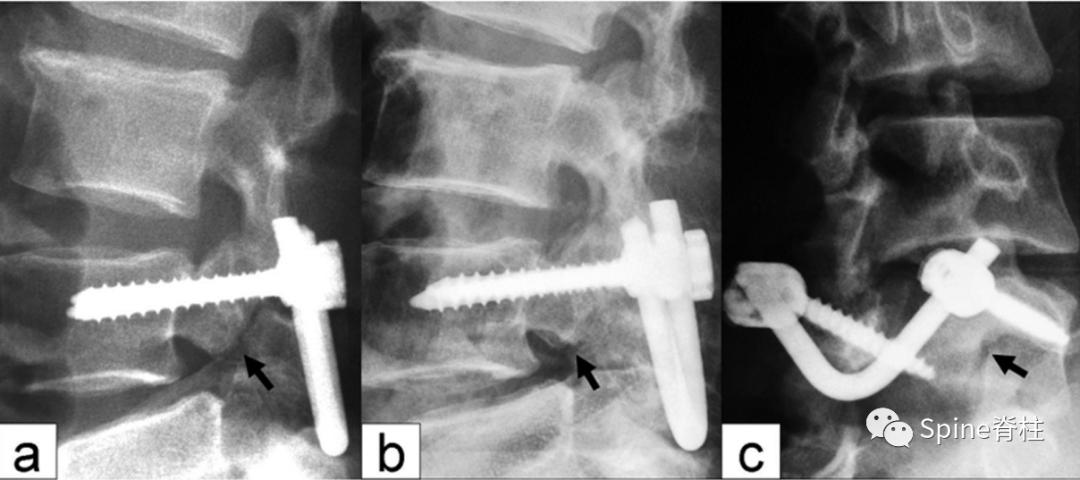

3. Patel于2012年提出的椎弓根螺钉+椎板螺钉

PMID: 22559277